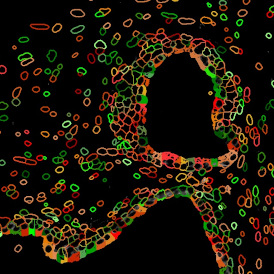

The IF Glomeruli App provides the detection of tissue, cells, and glomeruli stained by a specific marker. It segments the cells into their nucleus and/or cytoplasm and determines the cellular phenotype of specific IF-stained cell populations. The detected cells can be classified as being either inside or outside the glomeruli within certain distances (distance ranges are definable). For each cell, the spatial information and up to 20 intensity, statistics, and morphometric parameters are measured. The data can be displayed in diagrams and exported.